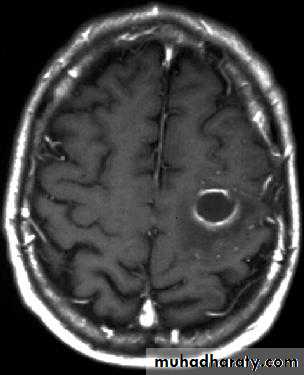

Brain Abscess CT with contrast

Neurosurgery

• They will show a single (or multiple) space occupying lesion that is well delineated with an enhancing wall, with variable surrounding oedema.

• The differential diagnosis of a single brain abscess in CT or MRI is a solitary metastasis, primary brain tumour or cerebral infarction.